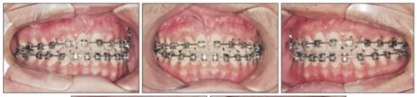

上頜前磨牙萌出后取出唇舌弓,上固定矯治器以排齊上頜牙列,該階段面弓暫時(shí)停止使用。

為最小化在青春后期上頜前傾,行骨支抗面弓(面弓聯(lián)合微鈦板[FM-MP])。在15歲1月時(shí)于雙側(cè)上頜骨顴突區(qū)植入兩枚微種植板,4周后加正畸力(500g/邊,與合平面呈30°向下,12-14時(shí)/天),持續(xù)3年5月。